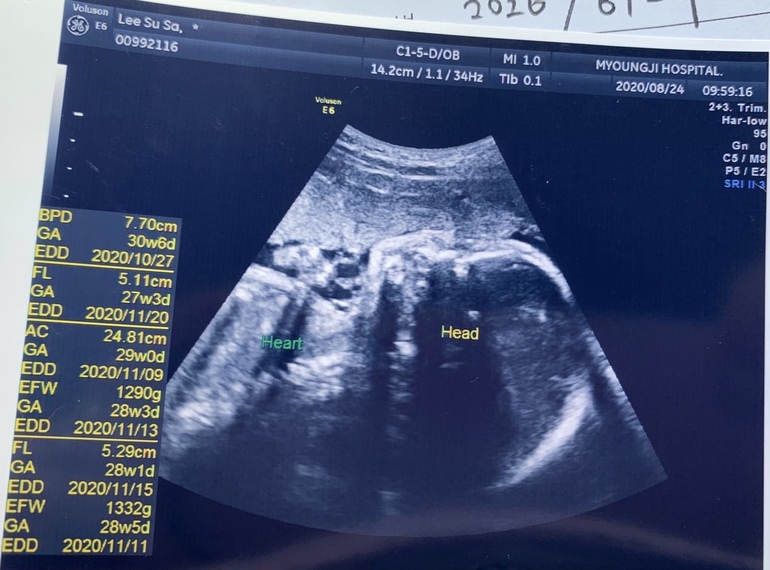

Немного расстроило УЗИ. Голову намеряли большую, а животик и ножки маленькие. К слову, это первый раз(!) когда нам смотрели что-то, кроме головы. Теперь переживаю, нормально ли это, а то начиталась всяких ужасов. Хотя врач, вроде, сказал, что подрастёт...наверное, зря переживаю, но как-то не спокойно.

Фото УЗИ и животик недели полторы назад